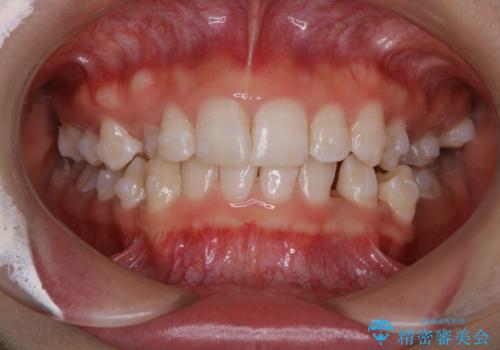

ワイヤー矯正治療中に気になる口臭をPMTCで予防

担当医 歯科衛生士